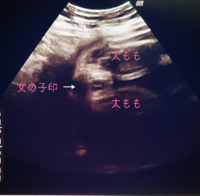

300g増えて2100gの女の子です。 胎動はあばら蹴り出して痛いです(笑) お腹が重くて寝づらくなりました。 次から1週間に1回の検診になります。 バースプランはビデオと写真だけかな。 NSTをするみたいです。 いよいよだなと実感がわいてきました。Mar 26, · 1 妊娠15週目のエコー写真です。 この時期は女の子でも突起物があるとのことで性別はまだわかりませんでした 2 17週のときのエコーですが、男の子、女の子どちらだと思いますか?(^^)1人目が女の子なので姉妹も憧 ;Dec 29, · √99以上 男の子 女の子 エコー 写真 葉っぱ 割れ目 乗鞍エコーラインの紅葉がまずまずとのことなので、久しぶりに(2年ぶりかな?)行ってみました。9月中旬頃に大雪渓あたりから始まる紅葉は、日を追う毎に下に移動。

妊娠24週でのエコー写真です 女の子でしょう とのことなのですが葉っぱ Yahoo 知恵袋

Feb 25, 21 · 19週で性別判明 男の子と確定したエコー写真 ぽむらいふ おうちと暮らしを楽しむ 胎児女の子エコー写真 胎児女の子エコー写真妊娠週0日(w0d)ごろの赤ちゃんのエコー写真です。投稿も募集しています。 何も見えないので女の子の可能性が高いですね、とNov 27, 11 · w2dのエコー写真です。先生にはお股に線がはっきり見えるし、突起物がないから8割女の子だと言われましたが、6ヶ月で分かるものなのか半信 半疑で上の子は男の子ではっきり映っていたのですが、このエコーは女の子ですかね?分かる方、是非意見を下さい!(>< 女の子だと思いMay 23, 18 · 特に 女の子は、男の子 赤ちゃんが女の子の場合でも、エコーで性別は確定できる!葉っぱマークや子宮が見える? 赤ちゃんの様子の分かりやすい3dエコー写真はママにとって記念になりやすく、普段赤ちゃんの存在を実感しづらいパパに見せるにも

Feb 07, 12 · エコー写真、これが葉っぱ? いつもお世話になっております。30w時いただいた写真になりますが、さっき見ていたら偶然足らしきものとおまたらしきものが写ってるエコー写真を発見しましてこの検診時は、逆子が治ったかどうかを特に重視していたので先生も私も性別についてApr 04, 16 · 妊娠6ヶ月のエコー写真について説明いたします。赤ちゃんの性別がわかるのもこの時期です。ウーマンエキサイトでは実際の妊娠6ヶ月のエコー(超音波)写真を使って不安をサポートしまJul 19, 19 · 22週の男の子のエコー写真 22周めの男の子の写真です。足が上下にあり、真ん中にシンボルが見えますね。 23週目の男の子のエコー写真 右上がお尻、左下にむかって2本の足が、その間にシンボルがしっかりと見えています。 24週の男の子のエコー写真